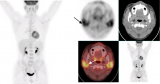

肾细胞癌(RCC)是最常见的肾脏恶性肿瘤,但转移模式有自己的偏好:最常见的是肺,其次是骨、肝。而转移到肾上腺,尤其是双侧同时转移,非常罕见。就在最近,西京医院核医学科主任康飞教授团队发表在《European Journal of Nuclear Medicine and Molecular Imaging》的病例报告则展示了一位肾癌患者的罕见病例:双侧肾上腺的转移灶,在CD70靶向 PET/CT和PSMA PET/CT上都表现为极高摄取。对于肾癌影像学来说,这是一件相当有意义的事情。01一个特别的病...